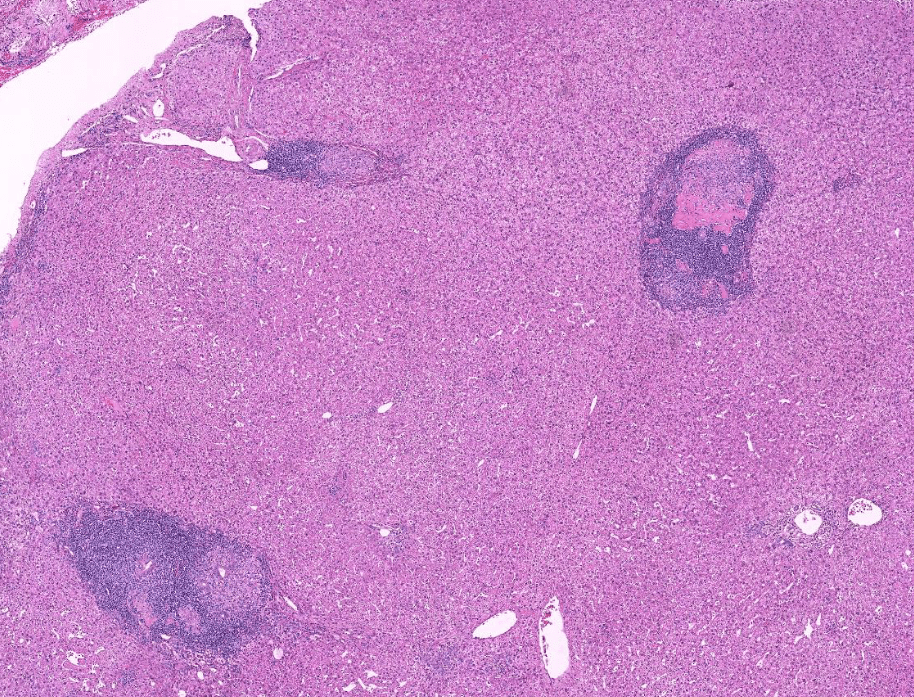

Organ: Lymph node

Diagnosis: Lymphoid hyperplasia

Descriptions:

- Increased number and size of follicles

- Follicles have distinct mantle zones and polarized germinal center

- Normal cell composition and tingible-body macrophages in the follicles